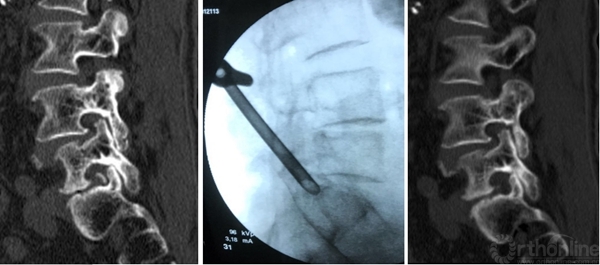

3D-CT:可观察骨性结构狭窄,如椎间孔区域狭窄,此类患者可行脊柱内镜下椎间孔扩大出口神经根减压治疗

术前造影显示后纵韧带完整性,术中保护后纵韧带

靶向穿刺